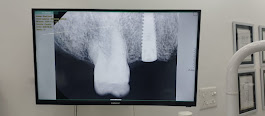

Dental implants have become one of the most reliable and long-lasting solutions for replacing missing teeth. If you’re considering this treatment, one of the most common questions is: “How long do dental implants last?” At Align & Smile Dental Care, Sector 18 Noida, we help patients restore their smiles with advanced implant technology designed for durability, comfort, and natural aesthetics. ⸻ 🦷 Average Lifespan of Dental Implants Dental implants are designed to be a long-term or even permanent solution. • Implant post (titanium root): Can last 20–30 years or more, often a lifetime • Crown (visible tooth): Typically lasts 10–15 years, depending on wear and care With proper oral hygiene and regular dental check-ups, many patients enjoy their implants for decades without issues. ⸻ 🔍 What Affects the Lifespan of Dental Implants? Several factors determine how long your dental implants will last: 1. Oral Hygiene Maintaining good oral care is essential. Daily brushing, flossing, and professional cleanings help prevent infections like peri-implantitis. 2. Lifestyle Habits • Smoking can reduce implant success rate • Teeth grinding (bruxism) can damage the crown • Poor diet may affect gum health 3. Bone Quality & Placement The strength of your jawbone and the precision of implant placement play a critical role in longevity. 4. Regular Dental Visits Routine check-ups allow early detection of any issues, ensuring your implant remains healthy. ⸻ ✅ Benefits of Long-Lasting Dental Implants Dental implants offer several advantages over traditional options: • Permanent and stable tooth replacement • Natural look and feel • Prevents bone loss • No impact on adjacent teeth • High success rate (over 95%) ⸻ ⚠️ Signs Your Implant May Need Attention While implants are durable, watch for these warning signs: • Pain or discomfort around the implant • Swelling or bleeding gums • Loose crown or implant • Difficulty chewing If you notice any of these symptoms, consult your dentist immediately. ⸻ 🏥 Why Choose Align & Smile Dental Care, Sector 18 Noida? At Align & Smile Dental Care, we combine expertise with advanced technology to ensure long-lasting results: • Experienced implant specialists • High-quality implant materials • Digital planning for precise placement • Personalized care for every patient Our goal is to give you a confident, healthy smile that lasts for years. ⸻ 💡 Tips to Make Your Dental Implants Last Longer Follow these simple steps to maximize the lifespan of your implants: • Brush twice daily with a soft-bristle toothbrush • Floss regularly or use interdental brushes • Avoid chewing hard objects (ice, pens, etc.) • Quit smoking • Visit your dentist every 6 months ⸻ 📌 Conclusion Dental implants are one of the most durable and effective tooth replacement options available today. With proper care and professional maintenance, they can last a lifetime, making them a worthwhile investment in your oral health. If you’re considering dental implants in Noida, visit Align & Smile Dental Care, Sector 18 for expert consultation and personalized treatment. ⸻ 📞 Book Your Consultation Today Ready to restore your smile? Contact Align & Smile Dental Care today to schedule your dental implant consultation and take the first step toward a confident, long-lasting smile.